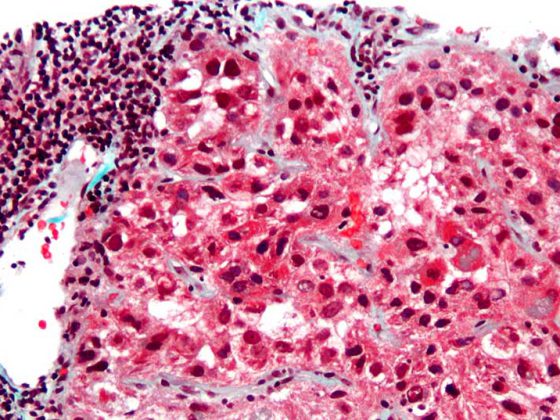

hepatocellular_carcinoma_intermed_mag

• Jahrestagung DGHO, OeGHO, SGMO und SGH+SSH in Stuttgart

Update hepatozelluläres Karzinom – Neues aus der Systemtherapie

• Gastroenterologie und Hepatologie

• Infektiologie

• Kongressberichte

• Onkologie